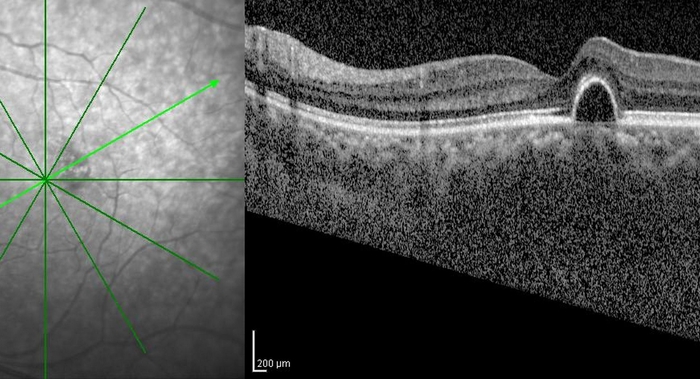

光干渉断層計(Optical Coherence Tomography: OCT)は、高解像度の断面画像を撮影するための新しい技術です。OCTイメージングは、超音波イメージングと似ていますが、音の代わりに光を使用します。OCTは、ミクロン単位の組織構造の断面画像を、その場でリアルタイムに得ることができます。OCTとカテーテルや内視鏡を併用することで、臓器の高解像度な腔内イメージングが可能です。OCTは、組織を採取して顕微鏡で検査する従来の病理組織学とは異なり、組織をその場でリアルタイムに撮影できるため、医療診断に適した画像技術です。OCTは、組織を採取して顕微鏡で検査する従来の病理組織検査とは異なり、その場でリアルタイムに組織の画像を得ることができるため、光生検のような使い方ができます。

また、遠視、近視、乱視、老眼などの視力障害の発生が増加していることから、OCTの需要が増加しています。さらに、ここ数年、ビタミンAの欠乏や事故の症例が大量に増加しています。OCTは、生きている眼の網膜と視神経の異なる層を可視化する優れた方法です。このような素晴らしい技術が発見される前は、患者さんが亡くなった後や眼球を摘出した場合にのみ、組織切片で眼球の様子を見ることができました。

世界の光コヒーレンス・トモグラフィー市場は、技術に基づいて、スペクトルドメインOCT(SD-OCT)とスウェプトソースOCTに分類されます。SD-OCTは、干渉縞パターンのスペクトル解析を用いて、後方散乱光の大きさと遅延に符号化された深さ方向の組織構造情報を提供する干渉計技術です。網膜や脈絡膜のイメージングでは、Swept Source光干渉断層計(OCT)が最新の技術です。スウェプトソースOCTでは、この技術で干渉パターンにフーリエ変換と呼ばれる処理を施すことで、すべての光のエコーを同時に測定することができます。